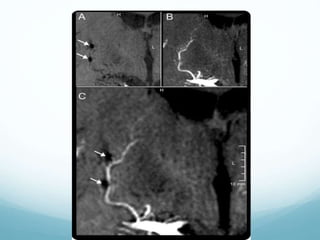

Figure CT scans Baseline noncontrast CT shows heterogeneous right deep parenchymal

hemorrhage (A).

Bermejo P G et al. Neurology 2010;75:834-834

Figure CT scansBaseline noncontrast CT shows heterogeneous right deep parenchymal hemorrhage (A). Bermejo P G et al. Neurology 2010;75:834-834 ©2010 by Lippincott Williams & Wilkins